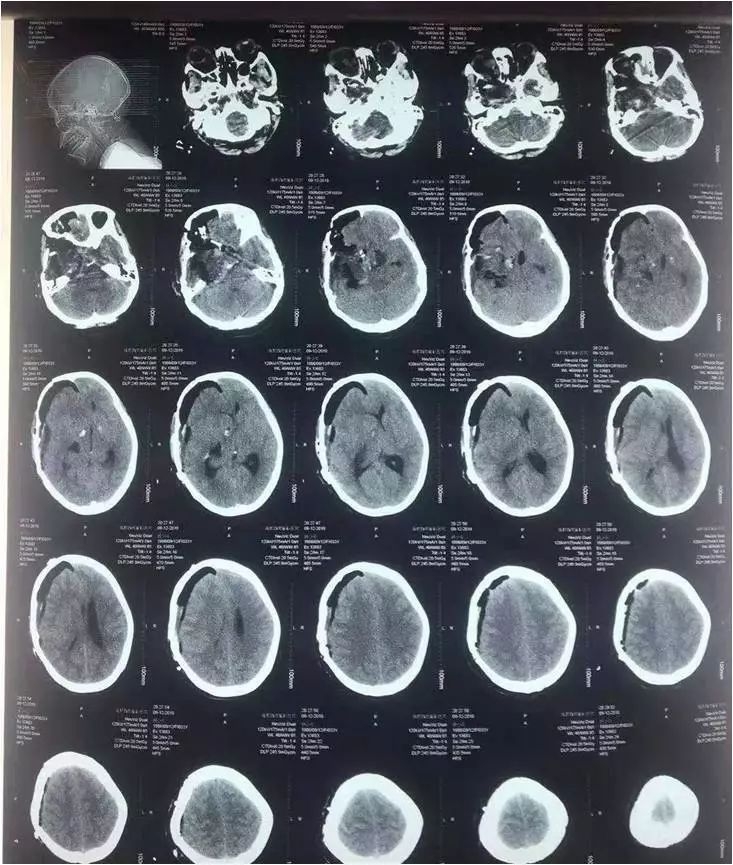

中脑海绵状血管瘤手术

术前

术后